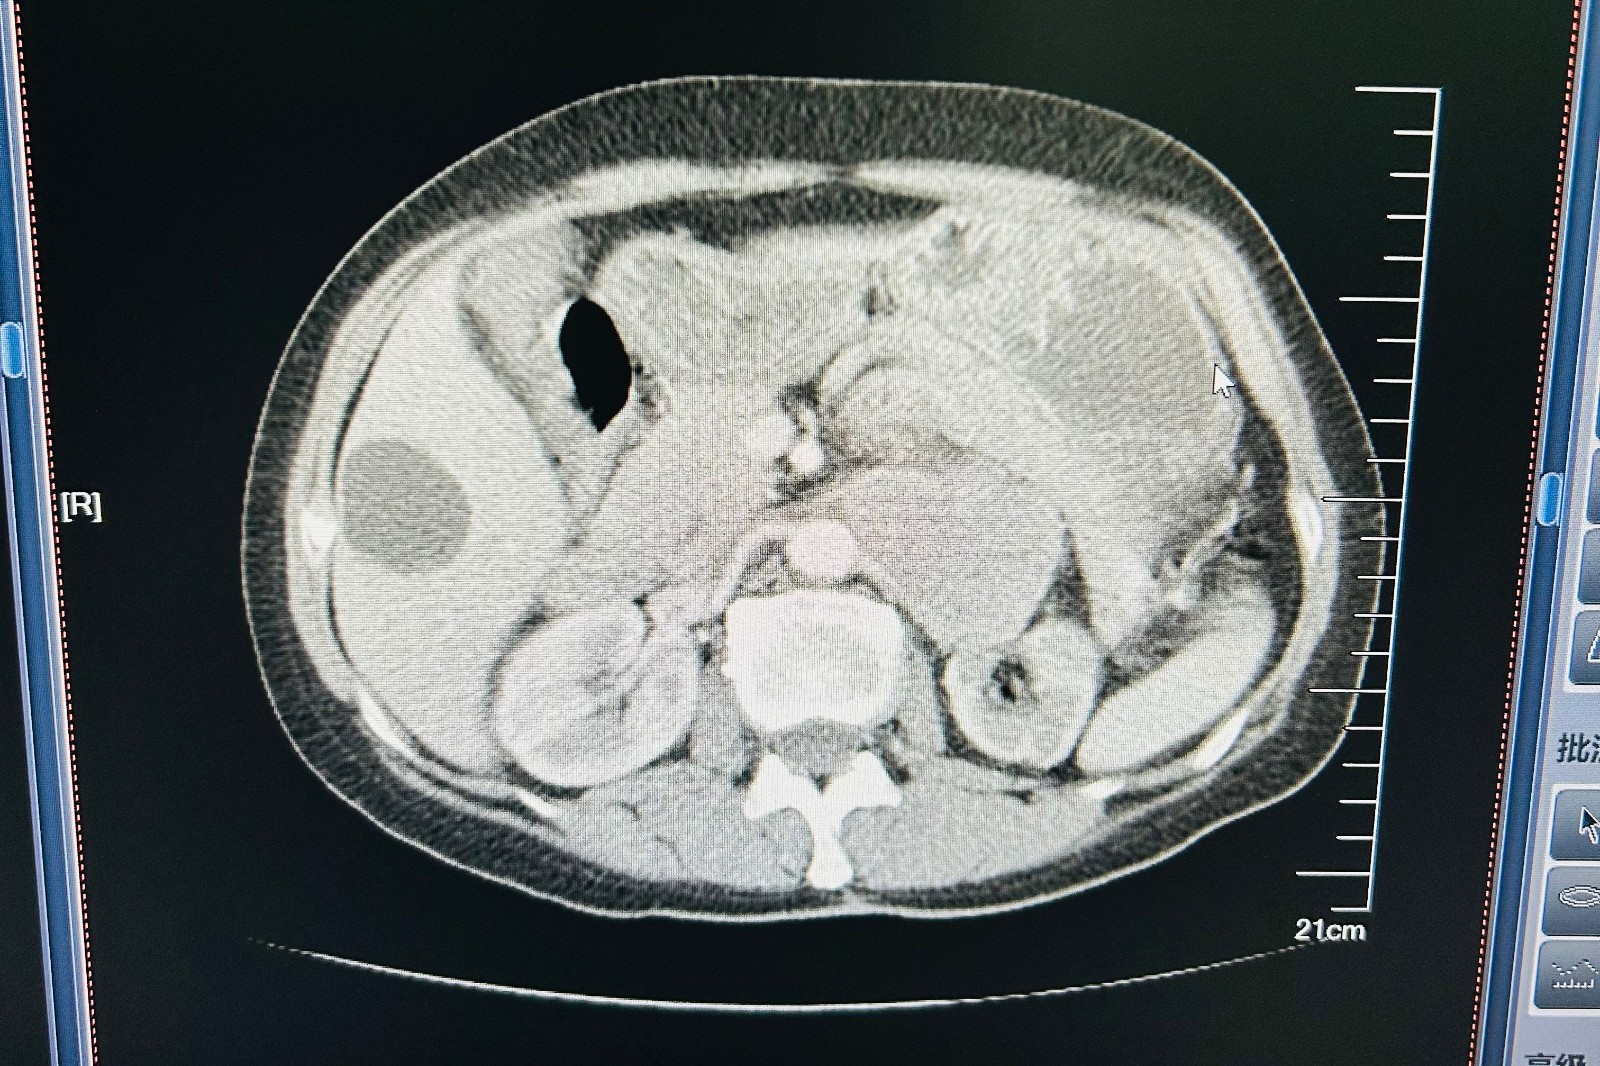

67岁的段女士,一年前因脑血栓住院治疗时发现血压升高,血压最高时190/130mmHg,一直口服降压药控制,近三个月出现多汗心悸,经我院多学科会诊明确为左肾上腺恶性嗜铬细胞瘤。段女士入院后抽血儿茶酚胺7项提示瘤体功能活跃;CT检查考虑肾上腺肿物为恶性,且瘤体与腹主动脉左侧、肾动静脉、胰腺和脾脏均有黏连;再加上患者既往有脑梗的病史,这些意味着手术难度很大,术中麻醉管理非常困难。

肿瘤巨大且瘤体与腹主动脉、肾动静脉、胰腺和脾脏均有黏连